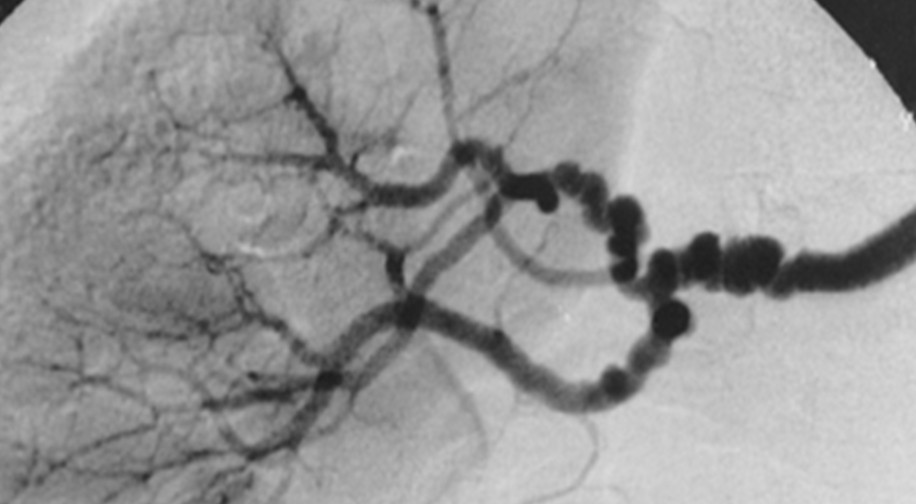

Fibromuscular dysplasia: Renal artery or carotid stenosis in young women Angiogram shows "chain of beads"

#USMLE pic.twitter.com/uU5nJ8F5iq